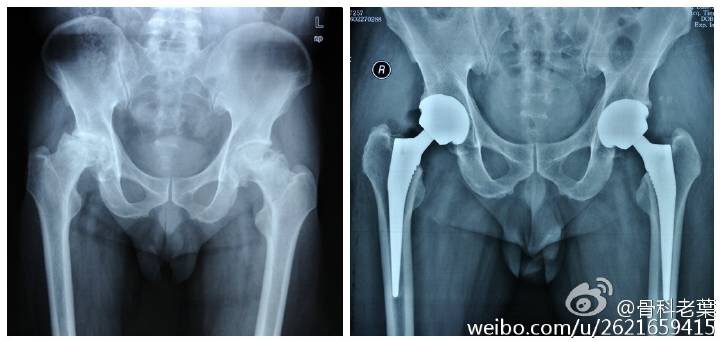

另附典型病例若干: